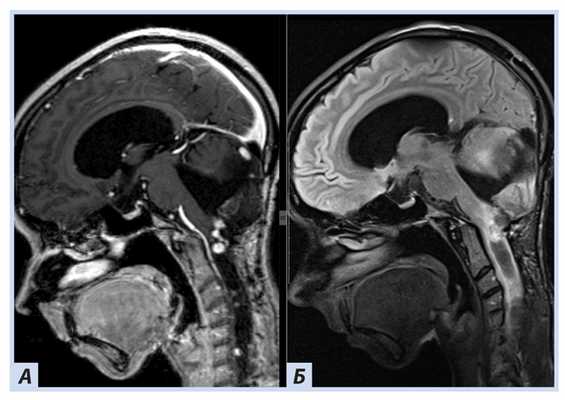

Лучевые методы. На МРТ-изображениях головного мозга выявлено характерное двустороннее поражение глаз (рис. 1), по данным КТ — с участками обызвествления (рис. 2). Также на КТ головного мозга были выявлены зона послеоперационных кистозно-глиозных изменений с наличием кисты и узла на уровне посттрепанационного дефекта в правом полушарии мозжечка, а также аналогичные зоны дорзальнее и в субкортикальных отделах; в левой гемисфере мозжечка определялись кистозные изменения (рис. 3).

Рис. 1. Пациентка П., 30 лет, с диагнозом «Болезнь Гиппеля−Линдау»: магнитно-резонансная томография головного мозга

Примечание. А, Б — Т2- и Т1-взвешенные изображения. В полости правой глазницы объемное образование с неоднородным МР-сигналом; В — постконтрастное Т1-взвешенное изображение, режим подавления сигнала от жира: определяется интенсивное, но гетерогенное контрастирование образования. Кровоизлияние в сетчатку справа.

Рис. 3. Пациентка П., 30 лет, с диагнозом «Болезнь Гиппеля−Линдау»: магнитно-резонансная томография головного мозга

Примечание. А — Tirm-режим: на фоне кист мозжечка визуализируется мягкотканный компонент, прилегающий к кисте справа; Б — DWI-режим: зона рестрикции диффузии по ходу стенки кисты справа; В — постконтрастное Т1-взвешенное изображение, режим подавления сигнала от жира: в той же зоне отмечается накопление.